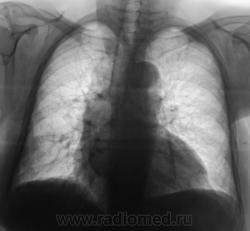

Пациент взят на контроль после флюорографии.

Произведено стандартное дообследование.

Рентгенограмма в прямой стандартной проекции.